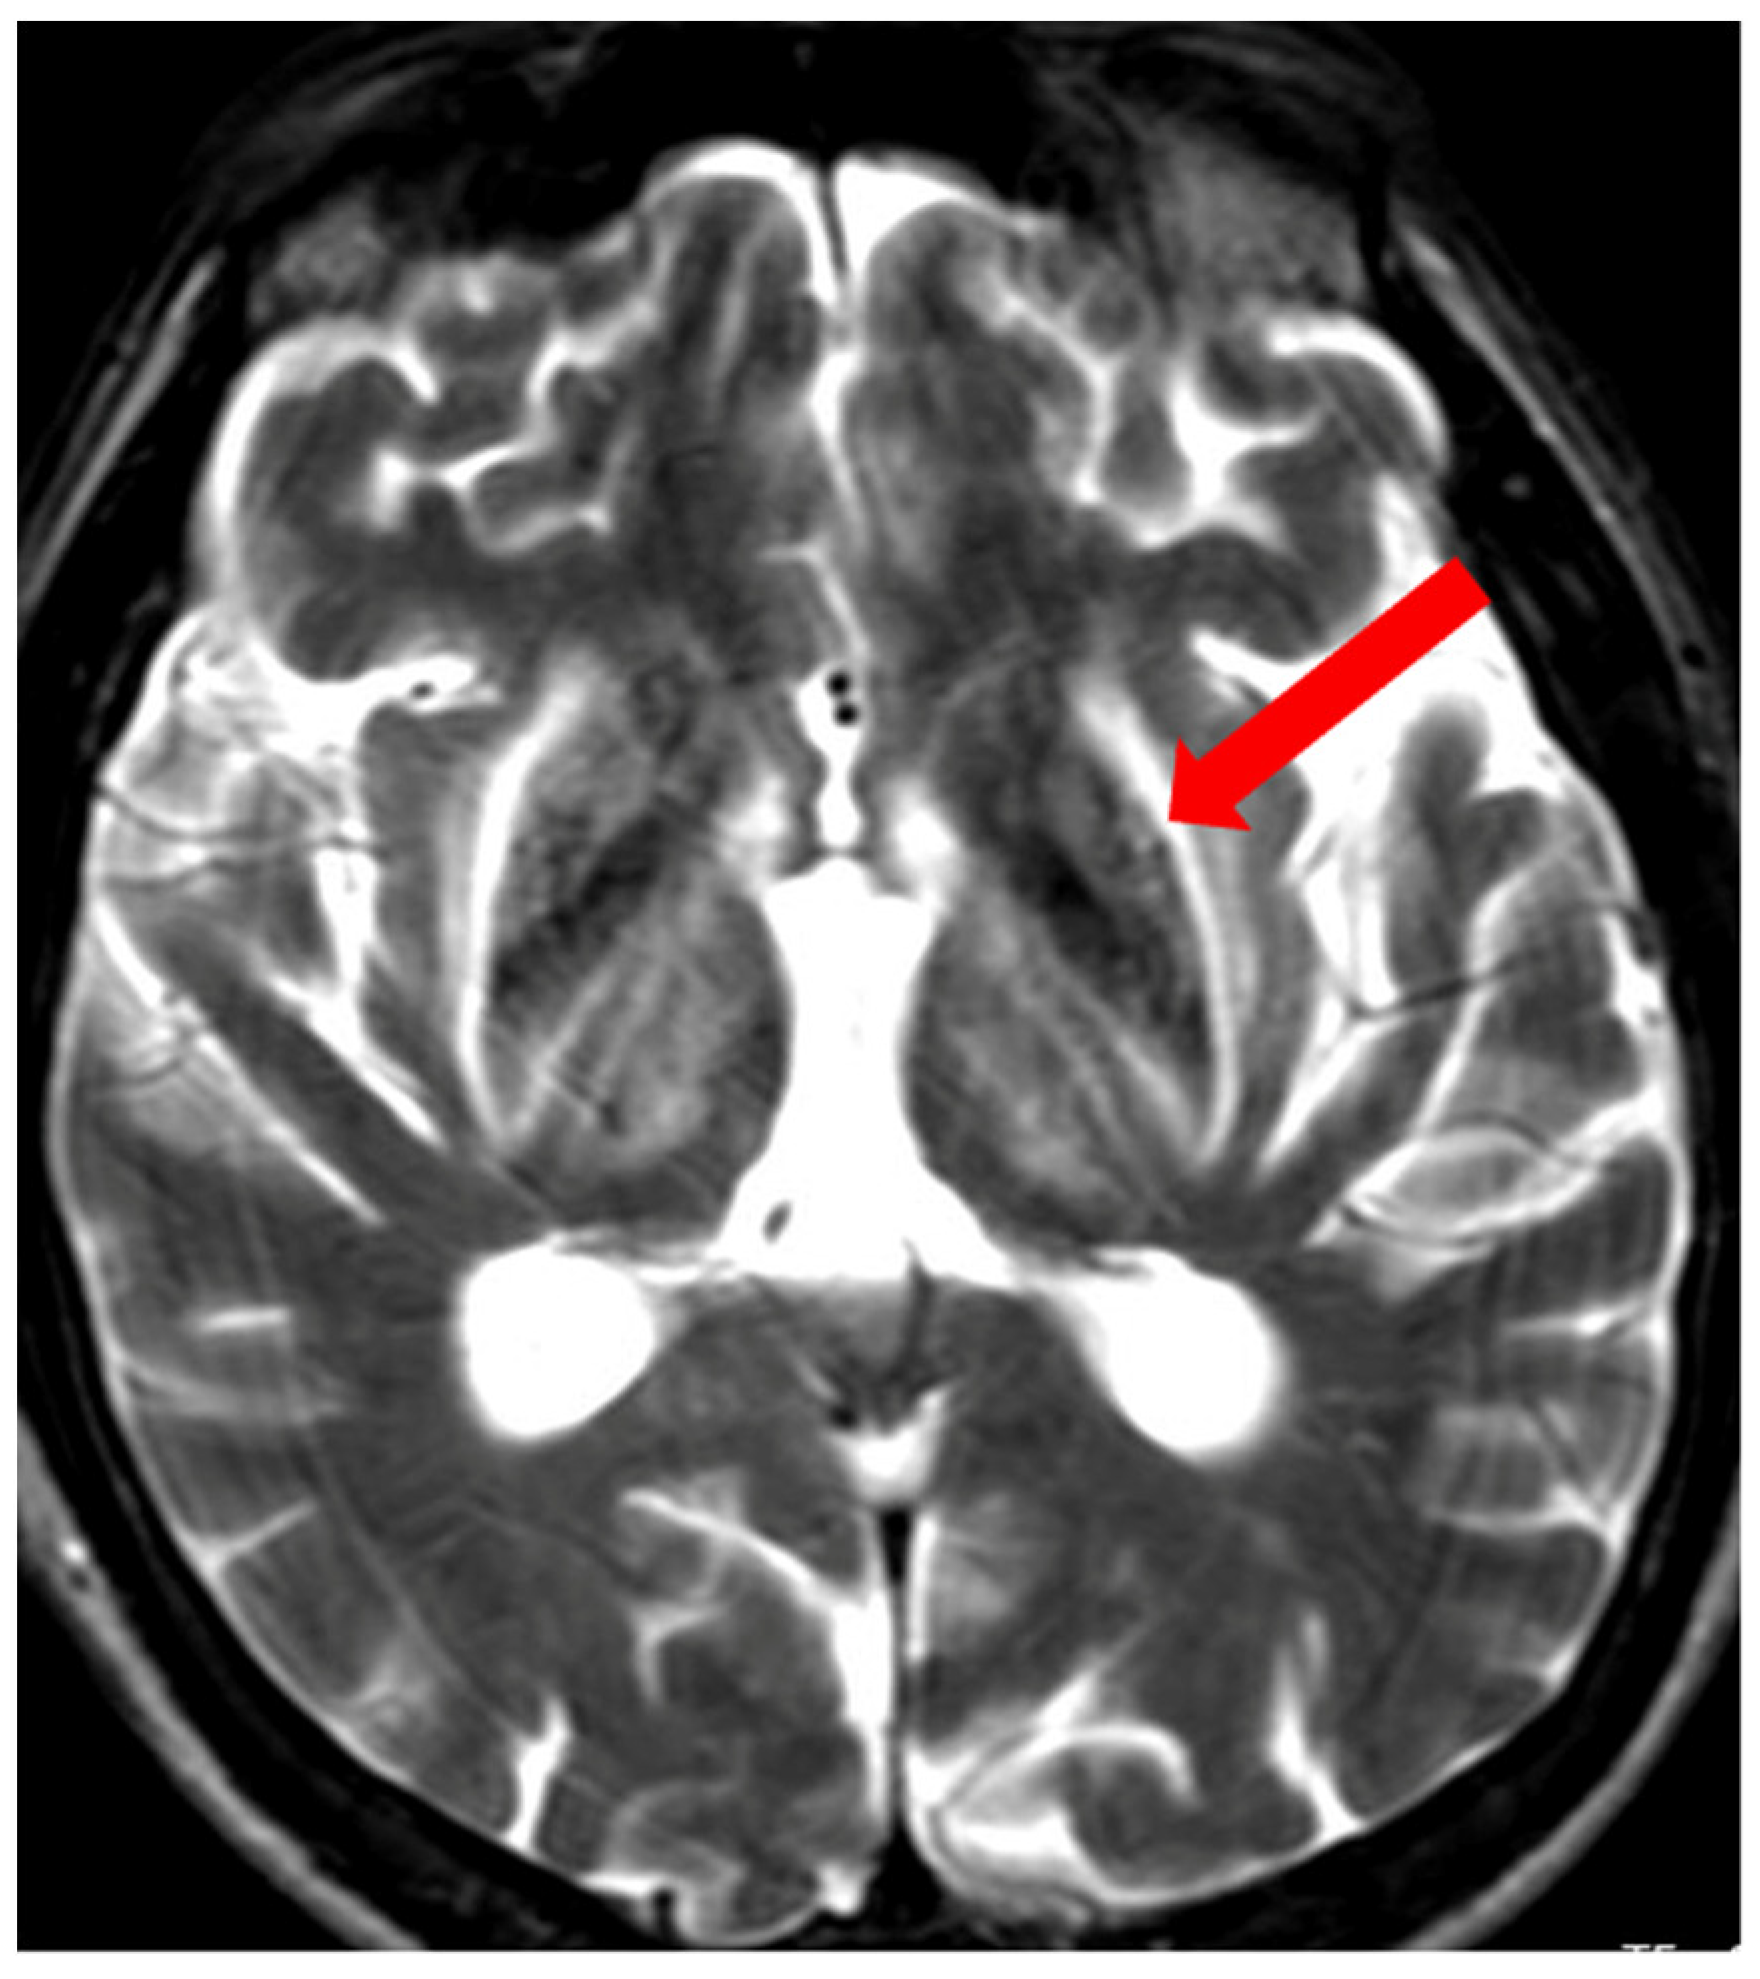

3.1. Classical Brain MRI Examination in WD Patients

5. Neuroradiological Pathognomonic Signs of WD